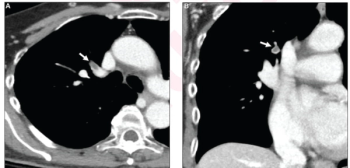

Cardiac CT angiography may provide insights on common post-op complications of left atrial appendage closure, ranging from peri-device leaks to device-related thrombus, according to research presented at the American Roentgen Ray Society (ARRS) conference.